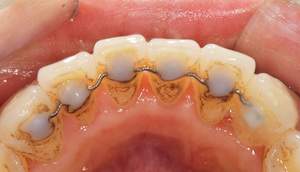

歯石除去、着色除去

治療前

治療後

| 年齢 | 25歳・女性 |

| 主訴 | 主訴:歯石除去、着色除去 治療部位:全顎 |

| 治療内容 | 初診検査・歯石除去・PMTC |

| 治療期間 | 60分 |

| 費用 | 合計約10,500円 初診検査約3,000〜4,000円 歯石除去約1,000円 PMTC5,500円(自費診療) (2024年6月現在) (歯の本数や検査内容で料金が変動します。) |

| リスク・副作用 | ・歯ぐきの炎症がある場合は歯石除去中に出血を伴う可能性があります。 ・処置後、知覚過敏が起こる可能性があります。 ・歯ぐきの炎症が治ると、歯ぐきが引き締まる為歯が長くなったと感じる事があります。 ・PMTCは歯を白くするものではなく着色・バイオフィルムの除去を目的としています。 |

| 治療方針 | 全顎的な歯石除去後、PMTCで着色とバイオフィルムを除去。 |

| 特記事項 | 矯正経験あり ホワイトニング経験あり |

| 担当者所見 | 歯石除去と前歯部の着色除去希望で来院されました。 下顎前歯の歯間部の歯石に対してフロス指導を行いました。 PMTCにより着色がなくなり、歯のトーンアップも感じられたと喜んでくださいました。 |